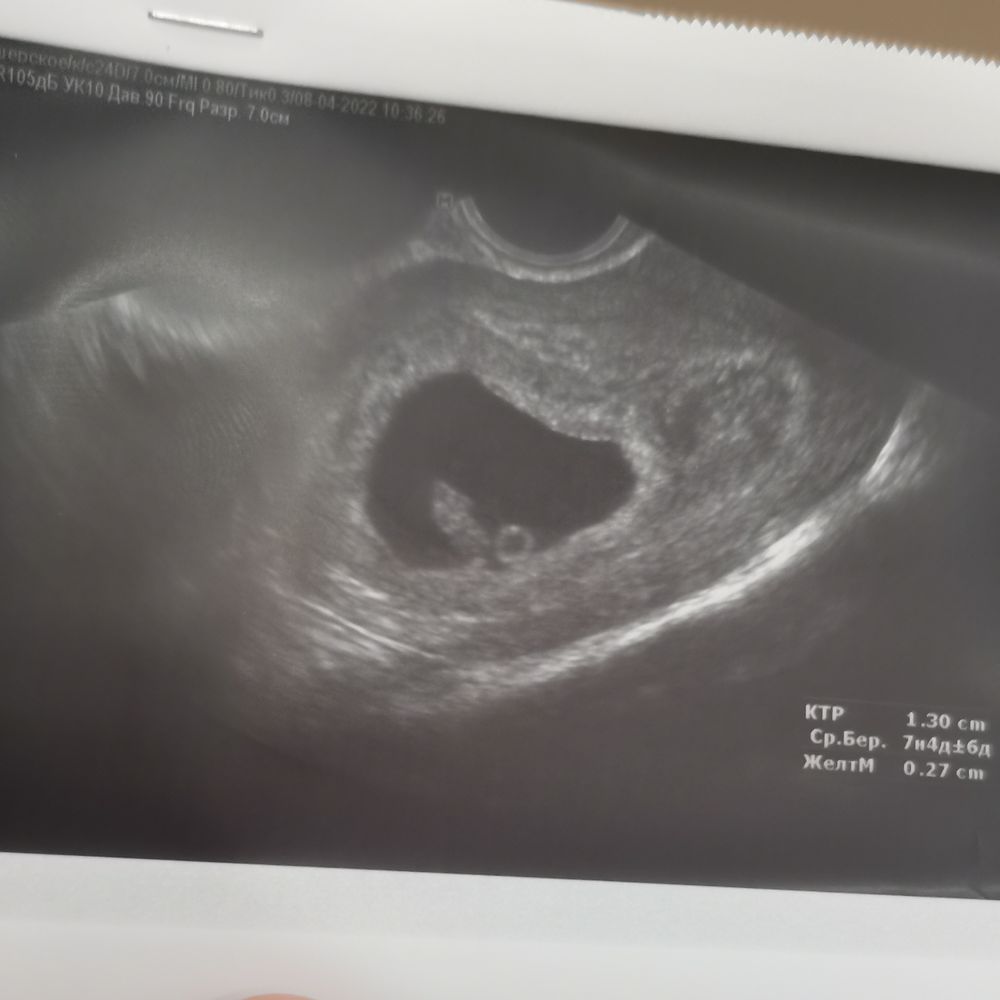

Гемостаз (+ИГ и ЛИТы)Девочки подскажите пожалуйста может у кого то тоже были такие результаты, вообщем беременность у меня после эко на данный момент 9-10нед,8 апреля первый раз сдавала тромбодинамику был срок 7-8нед,результаты не очень :скорость 43,3, задержка роста 0,8, начальная скорость 61,6,стационарная скорость 43,3,время появления спонтанные сгустков 19. Спустя 2 недели сдаю опять, и результаты ещё хуже. Колю клексан 0,4, 1 раз в день, и курантил 75 мг, подскажите у кого была плохая тромбодинамика что вы делали, как улучшить(((